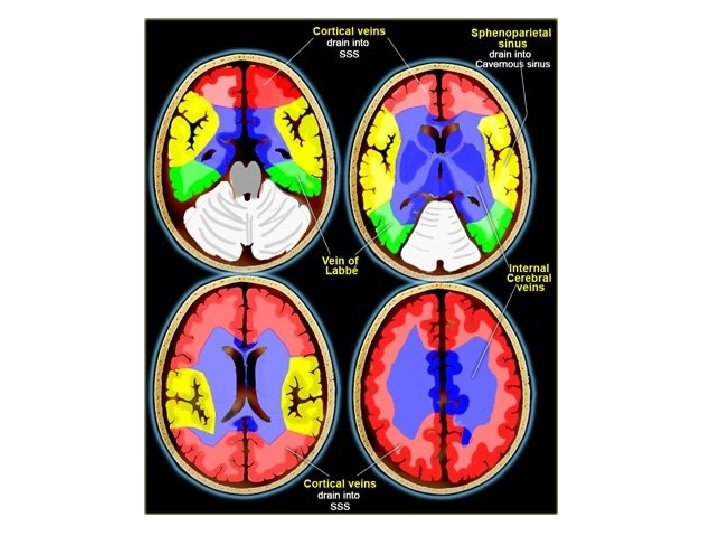

Lateral (A), anteroposterior (B), caudocranial (C), and oblique sagittal (D) MIP of CTA data set after MMBE. The projections demonstrate normal appearance of the superior sagittal sinus (arrowheads), the transverse sinuses (arrows), the deep venous system, and the superficial cortical veins without any overlying bone structures.